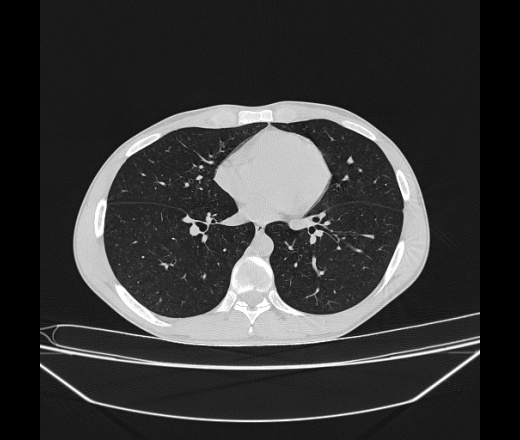

Молодой парень 18 лет, призывник, при прохождении ФЛС на верхушек левого легкого выявили очаги средней интснисвности с нечеткими контурами, тяжи. Сделали бок и томограммы 6-7-8. Везде описывают как очаговый твс. Вижу только перибронхиальный фиброз. Что за изменения в бронхах, указано нижи стрелками, тоже перибронхиальный?

Не стал бы говорить об очагах. Акцентировал бы не на фиброзе, а на тракционных бронхоэктазах. Не обязательно они результат tbc бронхов, но проверить не помешает.

Иван, пациент ведь уже "направлен с ОПТД", так?surprise Возвращайте его назад с заключением о возможном микобактериозе. Остаточные поствоспалительные ( посттуберкулёзные?) в дифряд.Очаговый твс с неясной активностью они уже себе "нарисовали", как я поняла.

+1 за микобактериоз.